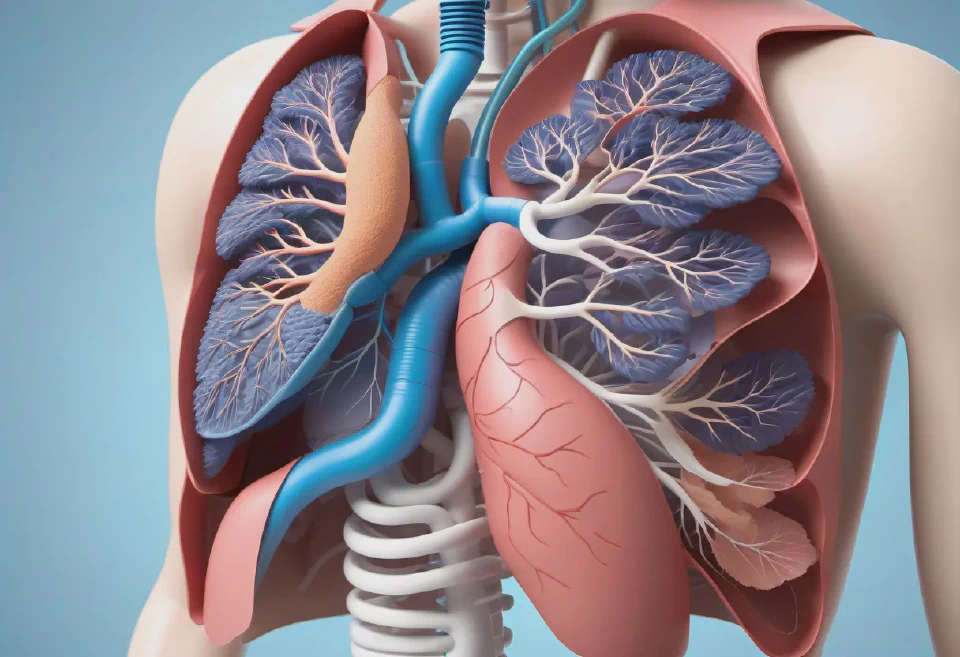

5. A futuristic, wearable health monitor being tested on a virtual human model engaged in different physical activities, such as running, swimming, and cycling, to showcase its durability, comfort, and accuracy in real-time health tracking.